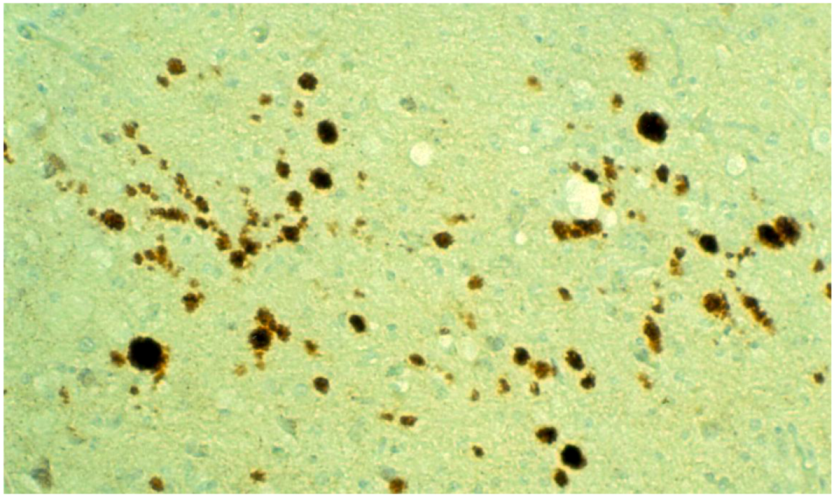

8. Neuropathology

- Piccardo, P.; Safar, J.; Ceroni, M.; Gajdusek, D.C.; Gibbs, C.J. Immunohistochemical localization of prion protein in spongiform encephalopathies and normal brain tissue. Neurology 1990, 40, 518–522. [Google Scholar] [CrossRef]

- Liberski, P.P.; Sikorska, B.; Lindenbaum, S.; Goldfarb, L.G.; McLean, C.; Hainfellner, J.A.; Brown, P. Kuru: Genes, cannibals and neuropathology. J. Neuropathol. Exp. Neurol. 2012, 71, 92–103. [Google Scholar] [CrossRef]

- Hainfellner, J.; Liberski, P.P.; Guiroy, D.C.; Cervénaková, L.; Brown, P.; Gajdusek , D.C.; Budka, H. Pathology and immunohistochemistry of a kuru brain. Brain Pathol. 1997, 7, 547–554. [Google Scholar] [CrossRef]